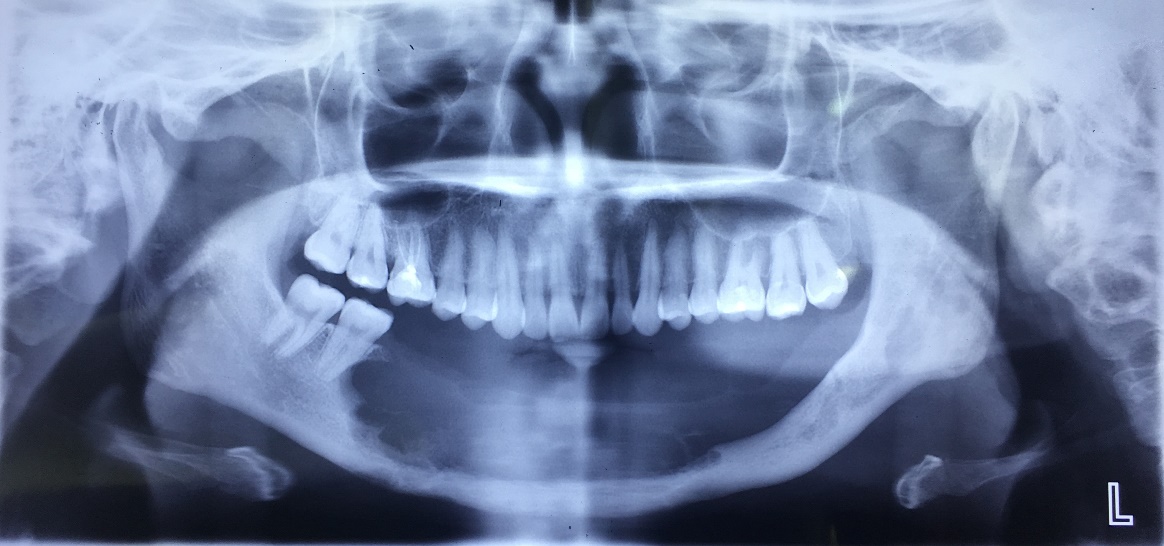

X-Quang sau cắt đoạn xương hàm dưới